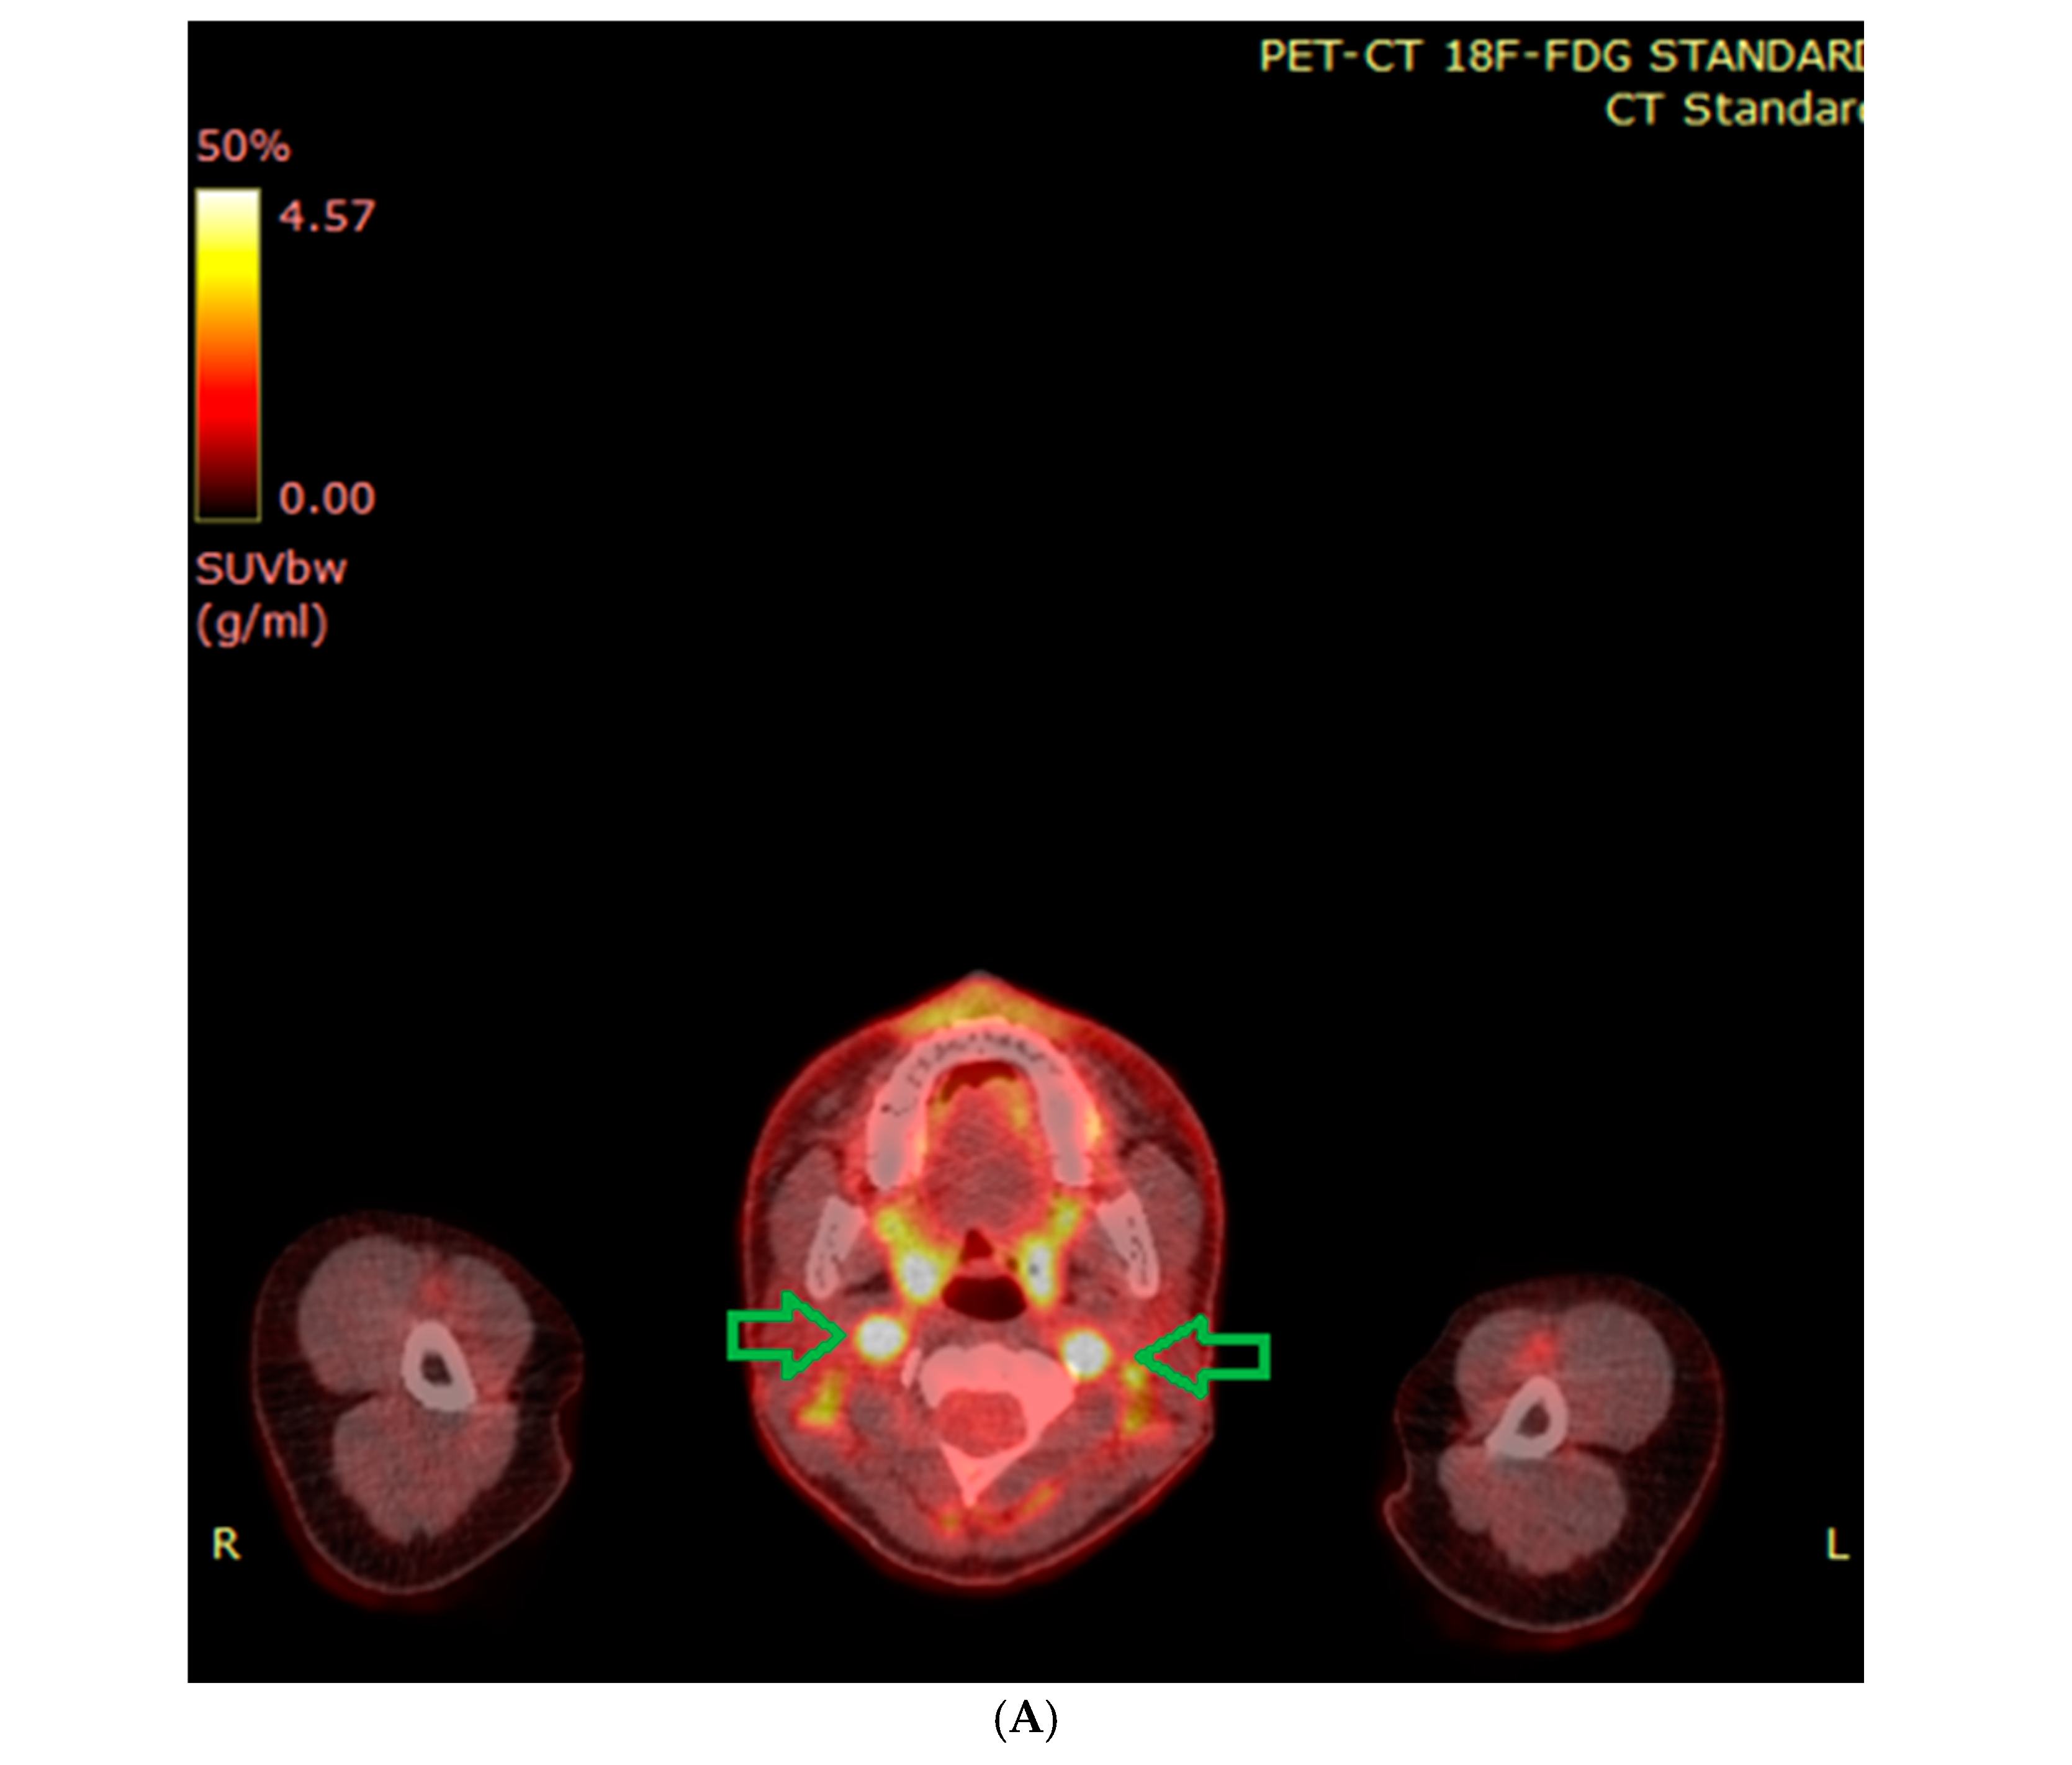

6.2. Functional Imaging